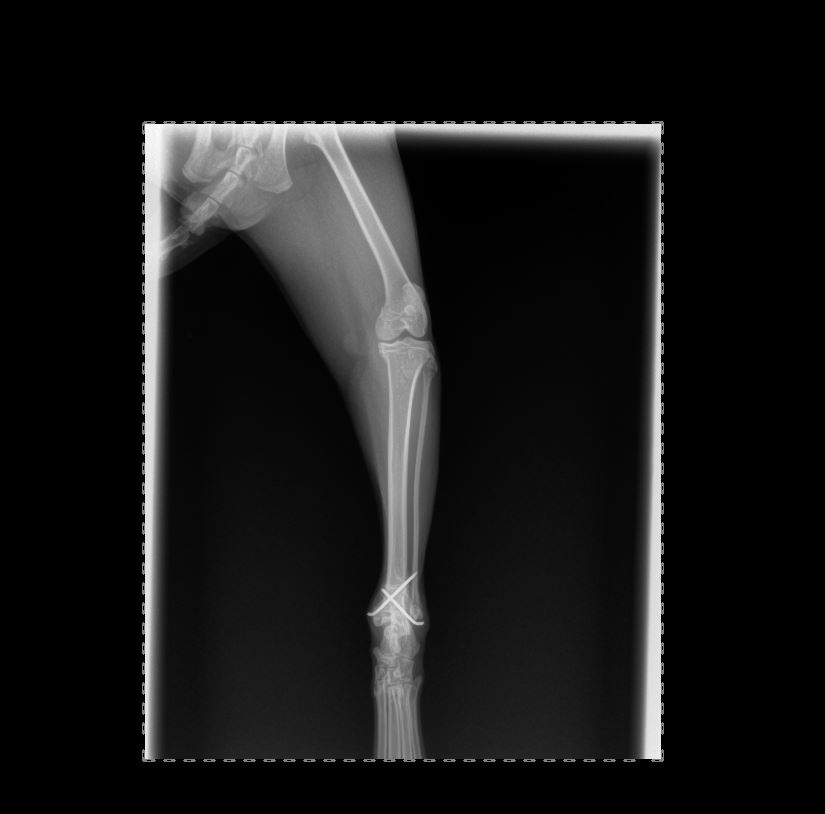

Chirurgies orthopediques:

-réduction des fractures (pose divers implants plaques broches etc),

Pose implant plaque DCP

Pose broche en "X" fracture femur en "Salter"